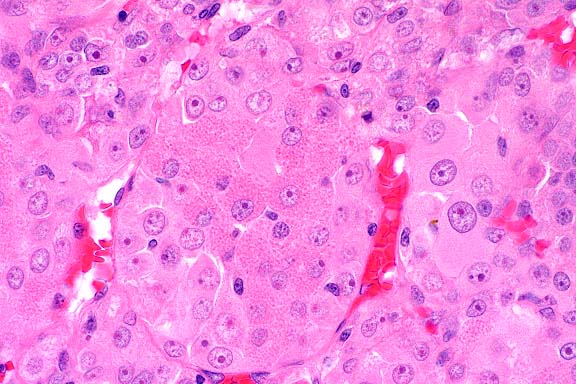

- Histologically, neoplastic tissue replaced most of the testis,

of some sections. The neoplastic cells were organized into tightly

packed sheets and large lobules divided by very fine fibrovascular

trabeculae with variably sized, scattered foci of necrosis that

often coalesced. Cells were large, and round to polygonal with

a round, normochromatic to hyperchromatic nucleus positioned

centrally or often eccentrically within a moderate amount of

eosinophilic, slightly granular cytoplasm. There was moderate

anisocytosis and anisokaryosis, and mitotic figures (which were

frequently bizarre) varied from 1 to 5 per high power field.

In many sections, clusters of neoplastic cells were seen within

peripheral blood or lymphatic vessels. Periodic acid-Schiff (PAS)

stains for glycogen revealed that most cells were negative with

slight patchy staining around the periphery of the nucleus in

some cells. Electron microscopy showed that the cells were very

undifferentiated and were not consistent with Sertoli cells or

Leydig cells, but contained some features of very early germ

cell differentiation. Immunohistochemistry revealed that the

cells were strongly positive for vimentin and S-100, but negative

for cytokeratins, neuron-specific enolase, placental alkaline

phosphatase and alpha fetoprotein.

- Case 13-2. Testis. Neoplastic polygonal cells with

brightly eosinophilic globular cytoplasm form pockets & nests.

- Conference Note: Conference participants had great

difficulty with this case. While the majority agreed with the

contributor's diagnosis of malignant seminoma, several favored

malignant interstitial (Leydig) cell tumor. An unencapsulated,

lobulated, densely cellular neoplasm with multifocal to coalescing

areas of necrosis replaces most of the testicular parenchyma.

The neoplasm is composed of polygonal to elongate cells arranged

in nests, packets, and variably broad cords supported by a fine

to moderate fibrovascular stroma. A key histological feature

present in some sections is packets and lobules of large polygonal

cells that have abundant, brightly eosinophilic, granular to

globular cytoplasm and round, centrally placed nuclei with prominent

nucleoli; these cells are interpreted as neoplastic Leydig cells.

Cells with features intermediate between the Leydig-like cells

and the poorly differentiated cells are also present.